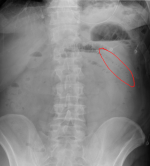

| B | • Bowel gas | • 3,6,9 rule - small bowel <3cm, large bowel <6cm, caecum and sigmoid <9cm |

| B | • Bones | • ribs, lumbar vertebrae, sacrum, coccyx, pelvis and proximal femurs |

| C | • Calcification • artifacts | • arterial Ca++, phelobliths, calculi • clips, tubes, implants |